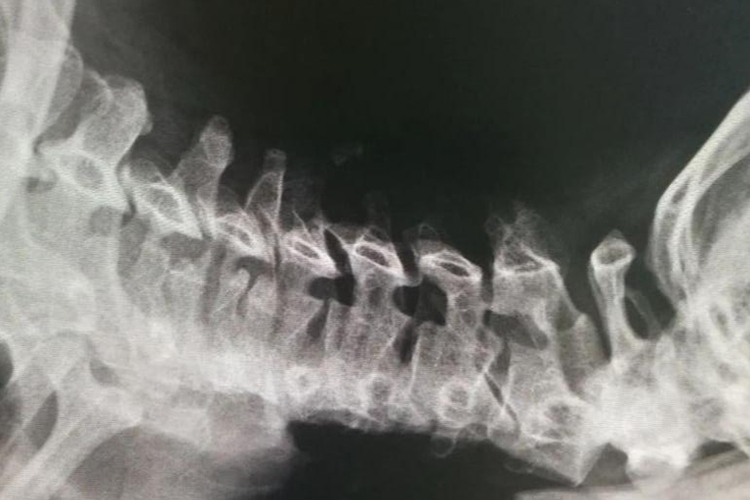

颈椎病颈椎生理曲度减小、消失或反弓,椎间隙狭窄,椎关节不稳,可有轻度滑脱。

神经根型颈椎病:椎体增生,颈椎关节增生,椎间隙变窄,颈椎生理曲度减小、消失或反弓,轻度滑脱,项韧带钙化和椎间孔变小。